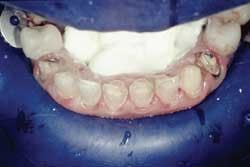

Rubber dam use is critical on mandibular teeth to isolate the lip and tongue and control moisture. Vanilla Bite (Discus Dental) was used to seal the lingual area (Fig. 1). Rubber dam use is also recommended for maxillary teeth. The preparations were cleansed with ConsepsisScrub (Ultradent) and a prophy cup (Fig. 2).